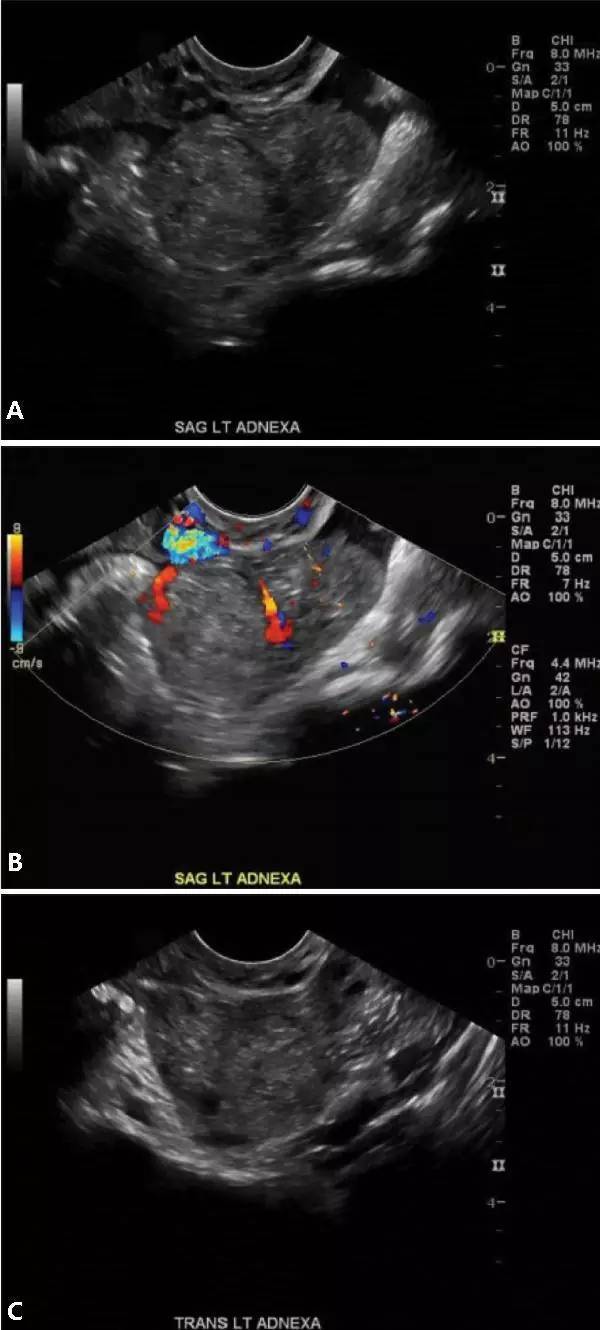

圖 7 卵巢妊娠聲像圖;矢狀切面(A 和 B)以及經陰道橫切面(C)圖像顯示左側附件區不均質回聲腫塊;彩色多普勒圖像(B)顯示左側卵巢內血供增多,提示存在異位妊娠